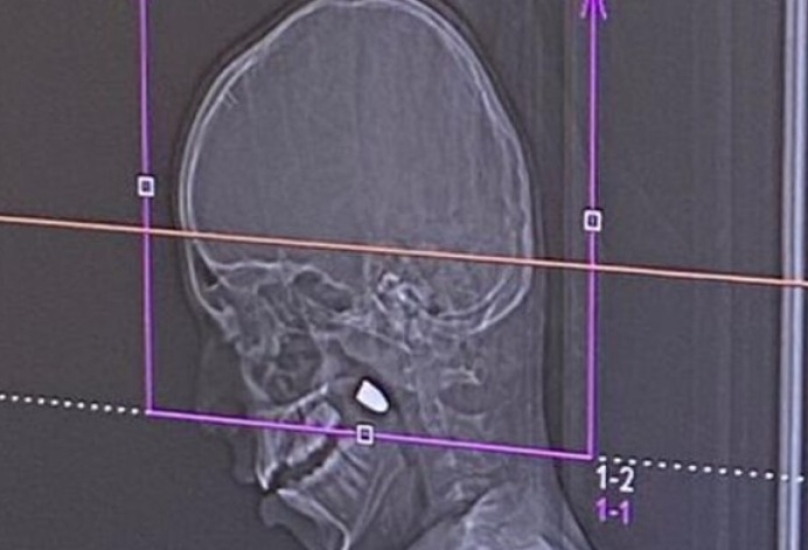

بدأت الواقعة حين صعد الطفل إلى سطح منزله لمشاهدة احتفالات العام الجديد، ليعود لعائلته مصاباً بنزيف في الوجه. وبعد فحوصات أولية في مستشفى "بوريا" كشف التصوير الطبقي ($CT$) عن وجود رصاصة مستقرة خلف الفك، تم نقله على الفور إلى مستشفى رمبام في حيفا نظراً لخطورة الحالة وحاجتها لتخصصات دقيقة.

تصريح طبي: أوضح الدكتور صالح نصير، الأخصائي في قسم جراحة الفم والفكين في رمبام، أن الرصاصة اخترقت عظام الجمجمة واستقرت في منطقة حساسة بالوجه، مؤكداً أن نجاح العملية دون مضاعفات عصبية يُعد "معجزة طبية"، حيث كان من الممكن أن تؤدي الرصاصة إلى أضرار دماغية دائمة.